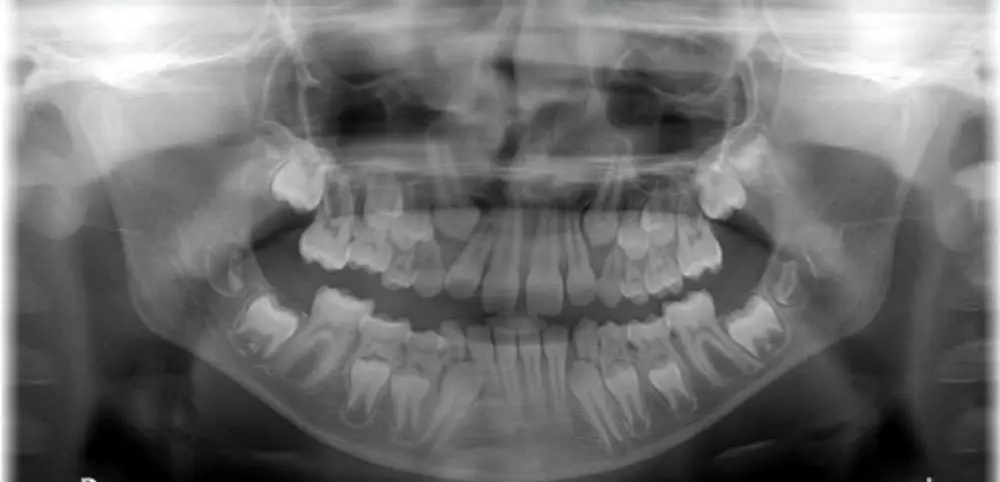

Patients with at least one maxillary permanent canine impaction. This was defined as when the canine to midline angle was less than 1.5 degrees on a panoramic radiograph.

The team followed the patients every 6 months. After 18 months a new panoramic radiograph was taken, and they evaluated the need for orthodontic treatment at this point.

The primary outcome measure was the canine position in terms of canine to midline angle, canine to first premolar angle, and other relevant measures. The secondary outcome was the time of any canine eruption and the need for further intervention after 18 months.

I have looked at their results by selecting what I think are simple outcome measures to interpret. I decided these were the sector of the canine on the radiograph. This was sector 0, which is a normal position for good eruption, whether the canine erupted before and after 18 months, and the complexity of any further orthodontic treatment.

If we look at the canine sector. They found that the sector only improved significantly in the expansion group. The percentage of canines in sector 0 at the start of the study was 65.7, and this increased to 85.7% at 18 months. However, I also spotted that the percentage of canines in sector 0 at the start for the no intervention short of space group was 96%. This looks very different from the start position of the expansion group.

Our RCT was performed in a group of children presenting with early mixed dentition (dental age 7.5-8.5y). At that young age maxillary canines are high up in line with the maxillary arch. They are not displaced to the palatal nor to the buccal, only in line with the arch. At that age, overlap with incisor roots is also very small and limited to sector 0 (normal position) or sector 1 (overlap with distal half of lateral incisor root). So both sector and bucco-palatal displacement in general are no issues in early mixed dentition. At this early age the alpha angle is the most predominant characteristic for diagnosing potentially impacted maxillary canines.